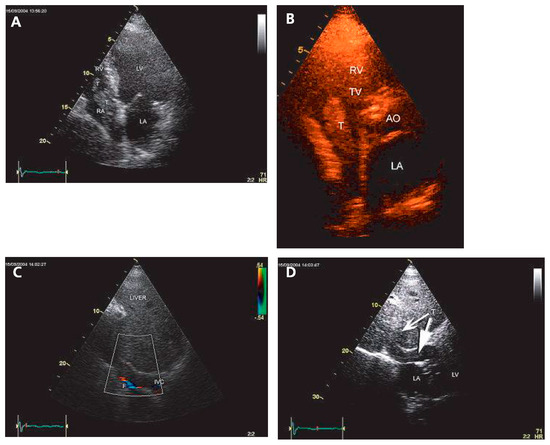

Echocardiographie et Sources Cardiaques d'embolie

• Ariel Cohen

Cardioembolic stroke is the second cause of ischemic stroke, with a high rate of morbidity and mortality. Echocardiography, mainly transesophageal echocardiography, is very useful for the diagnosis and risk stratification of the various potential car...